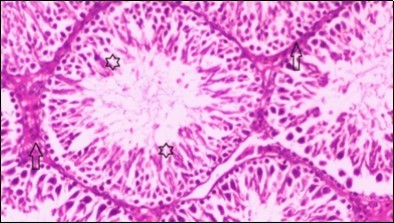

Histological examination of control rats' testis showed normal histological structure of the seminiferous tubules with an increase in the spermatogonia and other spermatocytes compared with the diabetic rats which showed an obvious decrease in the count of germinal cells generally and sloughing of germ cell in the lumen of seminiferous tubules in addition to absence of the mature sperms (Figure 3 and Figure 4). Rats tested of Fenugreek group and those treated with Glimepiride (Figure 5 and Figure 6) presented an increase in the number of spermatogenic cells and mature sperms with few focal necrotic cells. Whereas the combination therapy group showed normal histological structure of the seminiferous tubules with normal spermatogonia, presence of ledying cells and more mature of sperms (Figure 7). STZ reduced testosterone production, suggesting a decrease in the function of both Leydig (testosterone producing cell) and Sertoli (spermatogenesis) cells, which might be caused by a reduction in insulin secretion. These changes are probably due to increased Reactive Oxygen Species (ROS) production by accelerated Advanced Glycation End Products (AGE) formation 31 hexosamine and Protein Kinase C pathway. The administration of Fenugreek seeds to diabetic rats significantly decrease of sperm shape abnormality and improve the sperm count 32. Glimepiride reduced sperm abnormality and increased testis weights and sperm count by its antioxidant action 30. The potential protective efficacy of Fenugreek seed extract when added to Glimepiride was observed on reproductive systems.

Figure 7.Photomicrogragh of testis section of treated rat with combination of Fenugreek and Glimepiride showing nearly normal appearance of seminiferous tubules with organized spermatogenesis end with large number of spermatozoa (star). Note, Sertoli cells (arrows). (H&E) (40X).